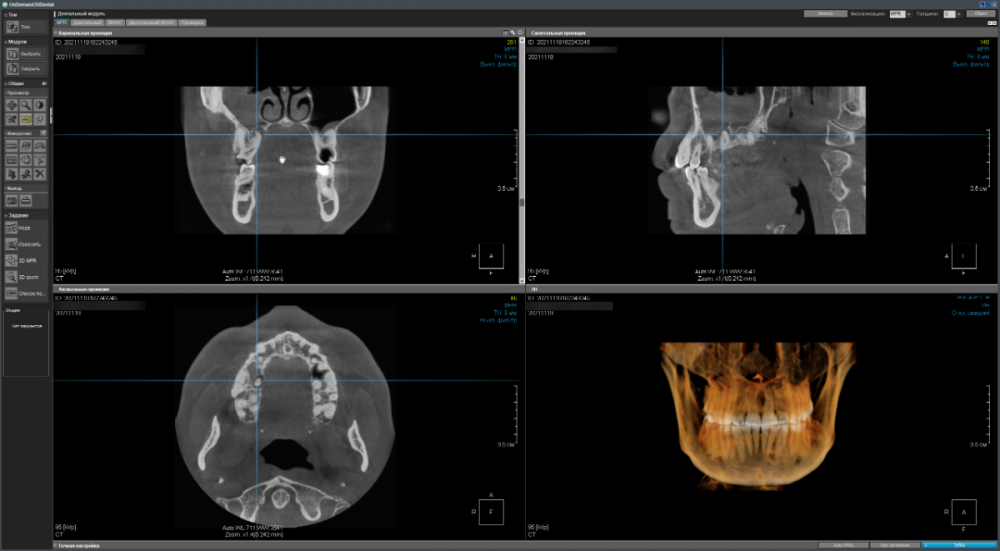

Имеется два сильно запущенных зуба на верхней челюсти справа - хотелось бы понять имеет ли смысл пытаться вылечить их терапевтически (чтобы потом поставить коронки) или уже поздно и надо/лучше удалить (и установить импланты)?

CDViewer_2IFjwB8Na7.png